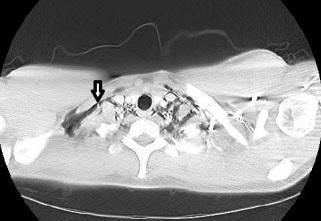

Chest x-ray films revealed diffuse parenchymal haziness and air tracking into the soft tissues of the neck, axilla, and the mediastinum (Figure 1). CT scan of the thorax revealed diffuse homogeneous distribution throughout both lungs of ground-glass opacities that suggested subacute hypersensitivity pneumonitis. Extensive pneumomediastinum (Figure 2a), and cervical emphysema (Figure 2b) were also noted on CT scan.